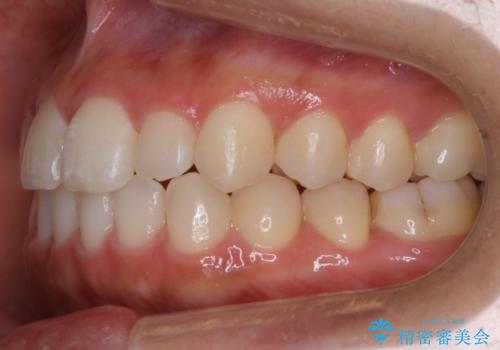

【非抜歯】部分矯正でも治る 前歯の反対咬合

- 前歯にガタつきを主訴にご来院されました。

奥歯の嚙み合わせに問題がほとんどみられなかったため、インビザライン ライトパッケージでの部分矯正を行うこととなりました。

今回のケースでは奥歯の噛み合わせに問題がほぼみられなかったため、前歯の位置のみに焦点を当て部分矯正を行いました。

適応されるケースが限られるものの、適応であった場合の治療期間は全体矯正と比べると格段に短くなり、費用も抑えられます。